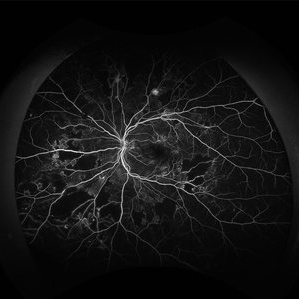

Proliferative Diabetic Retinopathy Angiography

Jan 22 2024 by Selene Rodríguez-Castro, MD

PDR

Photographer: Selene Rodríguez- Castro, APEC

Condition/keywords: background diabetic retinopathy (BDR)